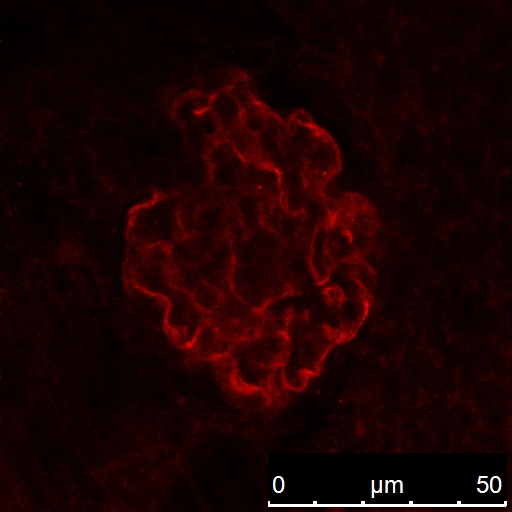

The podocin antibody Catalog No:113216 recognized the zebrafish pronephric glomeruli in zebrafish embryos(72 hour-old fish). IF result from Dr. Weibin Zhou.